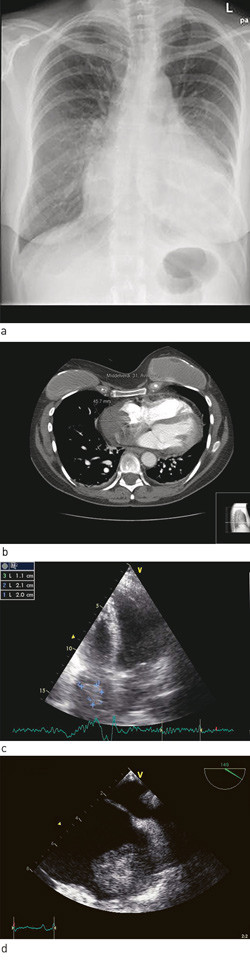

Røntgen thorax ga mistanke om perikardvæske (fig 1a). Dette ble verifisert ved ekkokardiografi, som viste væske i perikard rundt store deler av hjertet, med største bredde på 2,5 cm bak venstre ventrikkel. Venstre ventrikkel hadde gode kontraksjoner i alle avsnitt, noe som sammen med normale troponin T-verdier talte imot myokarditt. Imidlertid var høyre ventrikkels funksjon litt redusert, og det ble bemerket at høyre sides laterale vegg var fortykket. Pasienten ble dagen etter innleggelsen overført til regionsykehus på grunn av mistanke om truende hjertetamponade og ble tappet for 1 200 ml blodtilblandet perikardvæske.

Pasienten ble denne gang utredet med CT thorax, som viste en oppfylling i høyre forkammer (fig 1b). Denne ble gjenfunnet ved transtorakal ekkokardiografi (fig 1c). Videre utredning med transøsofageal ekkokardiografi viste en bredbaset oppfylling i høyre forkammer på 5,1 cm × 5,7 cm (fig 1d). Pasienten ble overført til regionsykehus for nærmere diagnostisering av oppfyllingen.